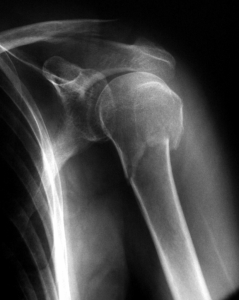

Tratamiento de las fracturas de Húmero

Una de las fracturas más frecuentes en traumatología es la fractura de húmero.  Se da a cualquier edad, pero sobre todo es más común en ancianos, debido a la osteoporosis y las frecuentes caídas que se producen en estas edades.